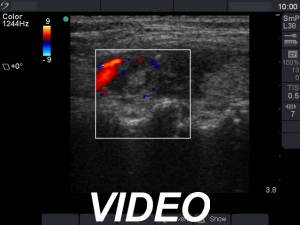

Ultrasonography. The thyroid was echonormal and presented several hypoechoic areas. The pattern in the right lobe was obviously focal form of lymphocytic thyroiditis.

A relatively large hypoechoic areas was found in the left lobe. The lesion had irregular borders. At first sight, this presentation of the left lobe could be interpreted as the central hypoechoic area-type form of lymphocytic thyroiditis. However, the hypoechoic lesion was not entirely surrounded with echonormal thyroid tissue. More importantly, the central hypoechoic areas-type form is almost always bilateral.

The sonographic pattern is remarkable. On the one hand, the tumor was identical to other more active foci of Hashimoto's thyroiditis. The only difference was the size of this lesion which was larger than other lesions observed in the thyroid. In the case of Hashimoto's thyroiditis neither the irregularity of border, nor the increased vascularization has any relevance. On the other hand, the tumor had microcalcifications and was significantly larger than other foci. The lesson to draw is the comparison of various lesions: if we detect a lesion which differs from others regarding the echogenicity, the size or the vascularization, it is advisable to perform FNA.